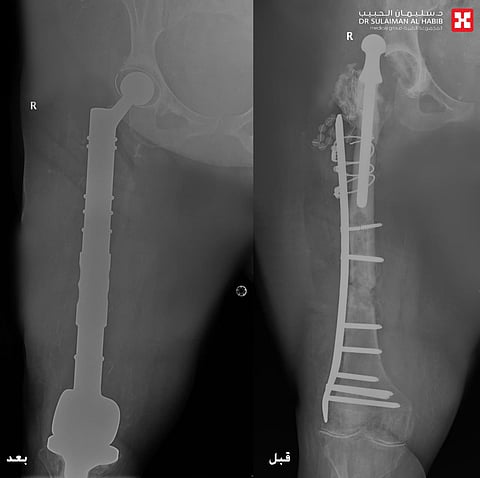

وتابع د. "الرفاعي" قائلاً أن الفريق الطبي وضع خطة علاجية متكاملة مكونة من عدة مراحل، بدأت بإزالة المفصل القديم والورم الالتهابي الذي بلغ وزنه "20" كجم، ووضع أجهزة داخلية تحتوي على مضادات لعلاج الالتهابات، وبعد التخلص منها، جرى استبدال كلي لمفصلي الورك والركبة، وعظمة الفخذ، في تدخل جراحي معقد استمر لـ"5" ساعات، وتكللت جهود الفريق الطبي ولله الحمد بالنجاح التام، حيث نقلت المراجعة بحالة صحية مستقرة إلى غرفة التنويم، وتحسنت حالتها باضطراد مع العناية الطبية الحثيثة، وغادرت المستشفى بعد عدة أيام بحالة صحية ممتازة، ولاحقاً تخلصت من كافة الأعراض التي عانت منها طوال سنوات ما قبل العملية، حيث جاءت إلى المستشفى بعد عدة أسابيع مشياً على قدميها.